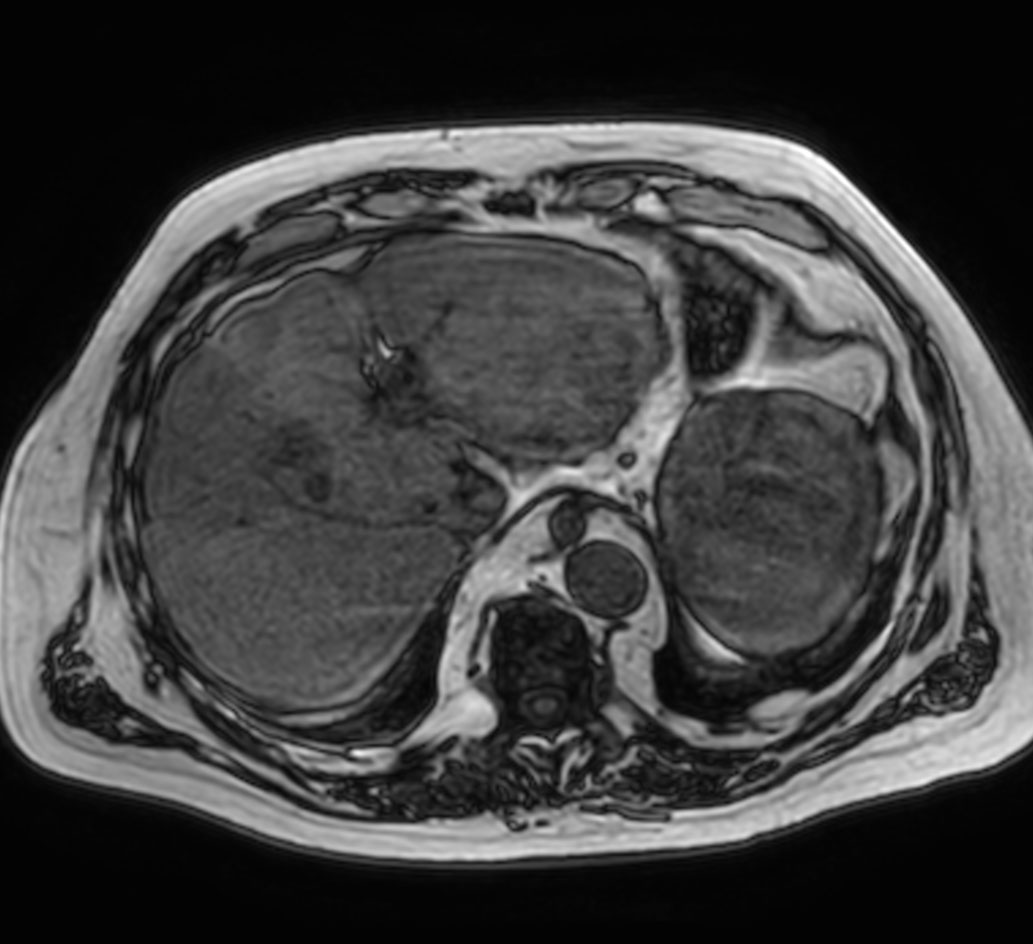

Axial T1w mDIXON XD (Water only)

Axial T1w mDIXON XD (In Phase)

Axial T1w mDIXON XD (Out Phase)